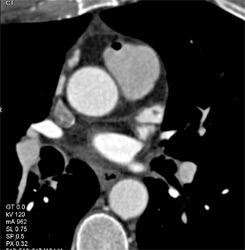

Pseudolesion in Bypass Graft Due to Cutoff of Top of Graft-area Not Scanned